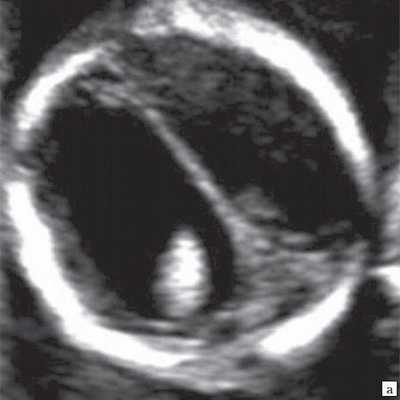

При изучении анатомии головного мозга плода в режиме 2D с применением стандартных аксиальных срезов во всех наших случаях мозжечок выглядел в виде овального образования однородной структуры с поперечным размером, менее уровня 5 процентиля для соответствующего срока беременности. При этом отсутствовала межполушарная выемка и область повышенной эхогенности по срединной линии мозжечка, характерная для отражения червя (рис. 1). На коронарном срезе также обращала внимание округлая однолобарная форма гипоэхогенного мозжечка (рис. 2). Использование трансвагинального подхода позволяло визуализировать дополнительно волокнистые структуры субарахноидального пространства (рис. 2).

Рис. 2. Корональные срезы головного мозга плода. Показан овальный контур мозжечка и волокнистые структуры субарахноидального пространства (стрелки).

а) Наблюдение 1, 3D.

б) Наблюдение 4, трансвагинально.